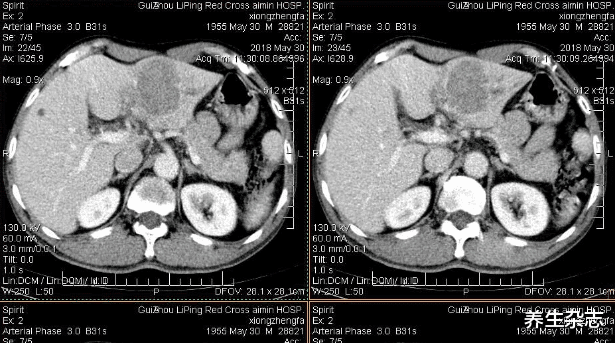

就在3个月前 , 小俞经常感觉到身体乏力 , 时不时的还感到腹痛 , 小俞以为是喝酒伤到了胃 , 便去医院做了检查 , 结果却被诊断为肝癌晚期 。